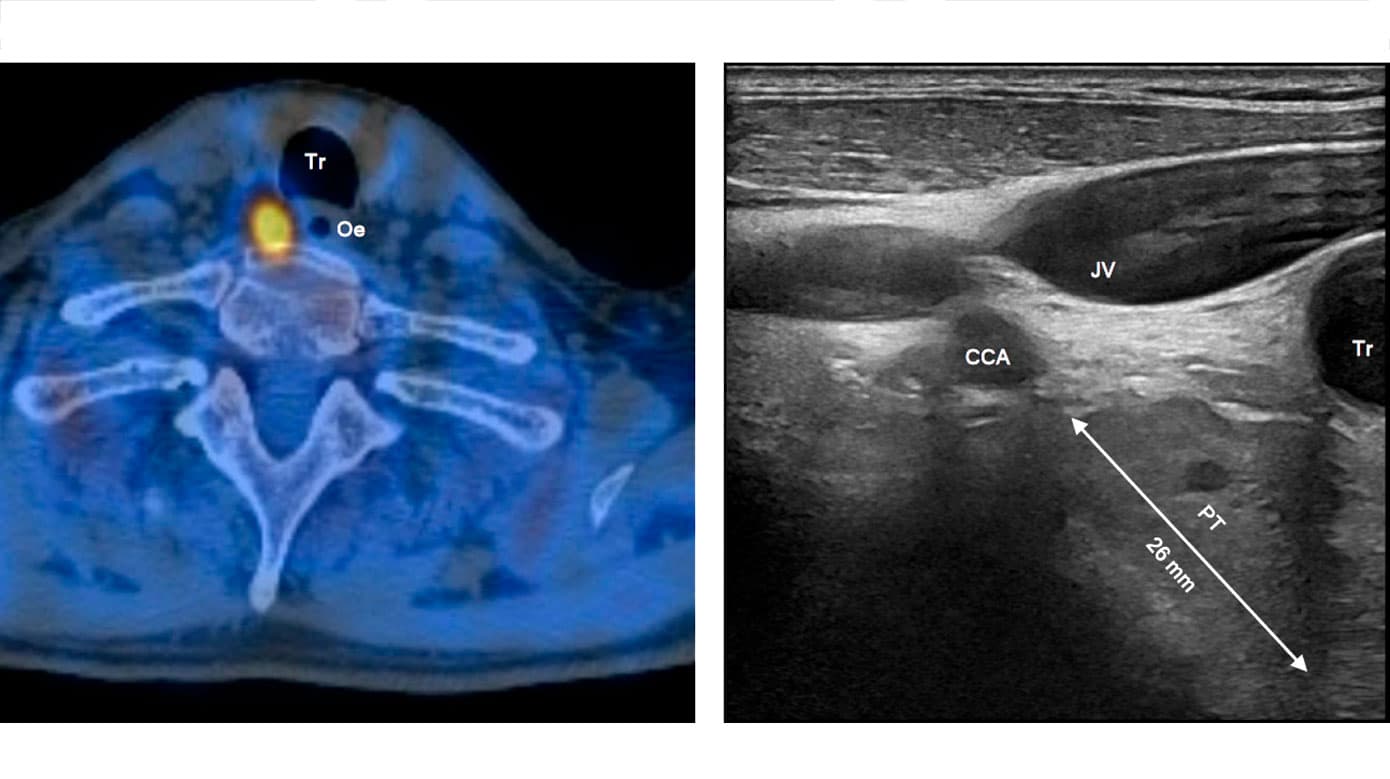

Modsat PET-skannere tillader gammakameraer simultan registrering af gammastråling med forskellige energier. Dette udnyttes ved dual isotopundersøgelser, hvor man sammenholder forskellige signaler i én optagelse og ved digital subtraktion fremstiller forskellene mellem dem. Det anvendes bl.a. ved lungeventilations- og perfusionsskintigrafi samt ved parathyroideaskintigrafi som vist i Figur 4.

Tomografiske (tredimensionelle) billeder bliver til efter rekonstruktion af rådata optaget hele vejen rundt om patienten og kræver højere aktivitetsmængder for et passende forhold mellem signal og støj. Ved hybridbilleddannelse kombineres en single-photon emission computed tomography (SPECT) med en CT, og resultatet er både en anatomisk lokalisation af sporstofoptagelsen og en dæmpningskorrektion, der skalerer signalerne efter vævsdybde. Et eksempel ses i Figur 3.